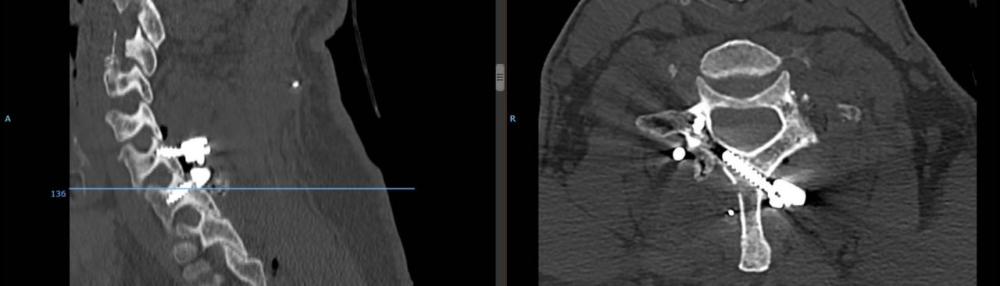

وأوضحت المدينة أن المريض كان يشكو من آلام في الرقبة مصحوبة بخدران وتنميل وضعف في عضلات اليد اليسرى، مشيرة إلى أن الفريق الطبي بقيادة استشاري العمود الفقري الدكتور معتصم عبيدات، أجرى عملية جراحية لإرجاع الانزلاق في الفقرات وتثبيت الفقرتين من الخلف باستخدام البراغي والقضبان المعدنية وهي تقنية حديثة ومميزة بتثبيت الفقرة السابعة، حيث تم وضع أحد البراغي في الصفيحة العظمية.